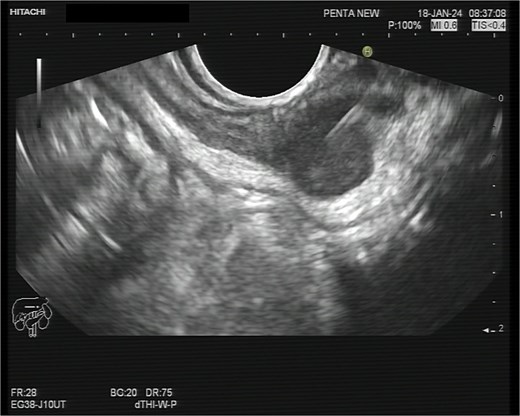

A 75-year-old woman with a past surgical history of serous papillary ovarian carcinoma underwent complete debulking surgery and adjuvant chemotherapy treatment 2 years prior to her current presentation. During follow-up, increased FDG uptake along with a 1.2-cm mass was seen on a PET-CT on the serosal surface of the recto-sigmoid junction (Fig. 1). An attempt was made to evaluate the lesion using trans-rectal sonography. Radial sonographic view showed a 12 mm, hypoechoic, well-defined lesion located at the serosal surface of the recto-sigmoid junction (Fig. 2). After reverting to a linear view, the lesion was sampled with fine-needle biopsy (Fig. 3) and whitish thick cores were retrieved (Fig. 4). The procedure was uneventful and no adverse events were noted. Pathology revealed fragments of high grade serous carcinoma of tubo-ovarian origin. Relying on the histological information gained from the biopsy, it was known that the lesion although not obvious to the eye during surgery, had to be found and resected. The surgical procedure was challenging with multiple adhesions, which made it difficult to locate the lesion. Based on the valuable preoperative knowledge, the patient was able to have a complete debulking of the tumor mass.

Whitish core material obtained by fine-needle biopsy embedded on a slide before submission to pathological evaluation.